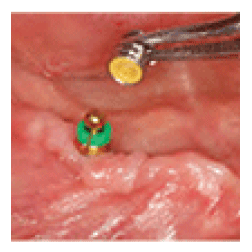

Placement of Healing Cap